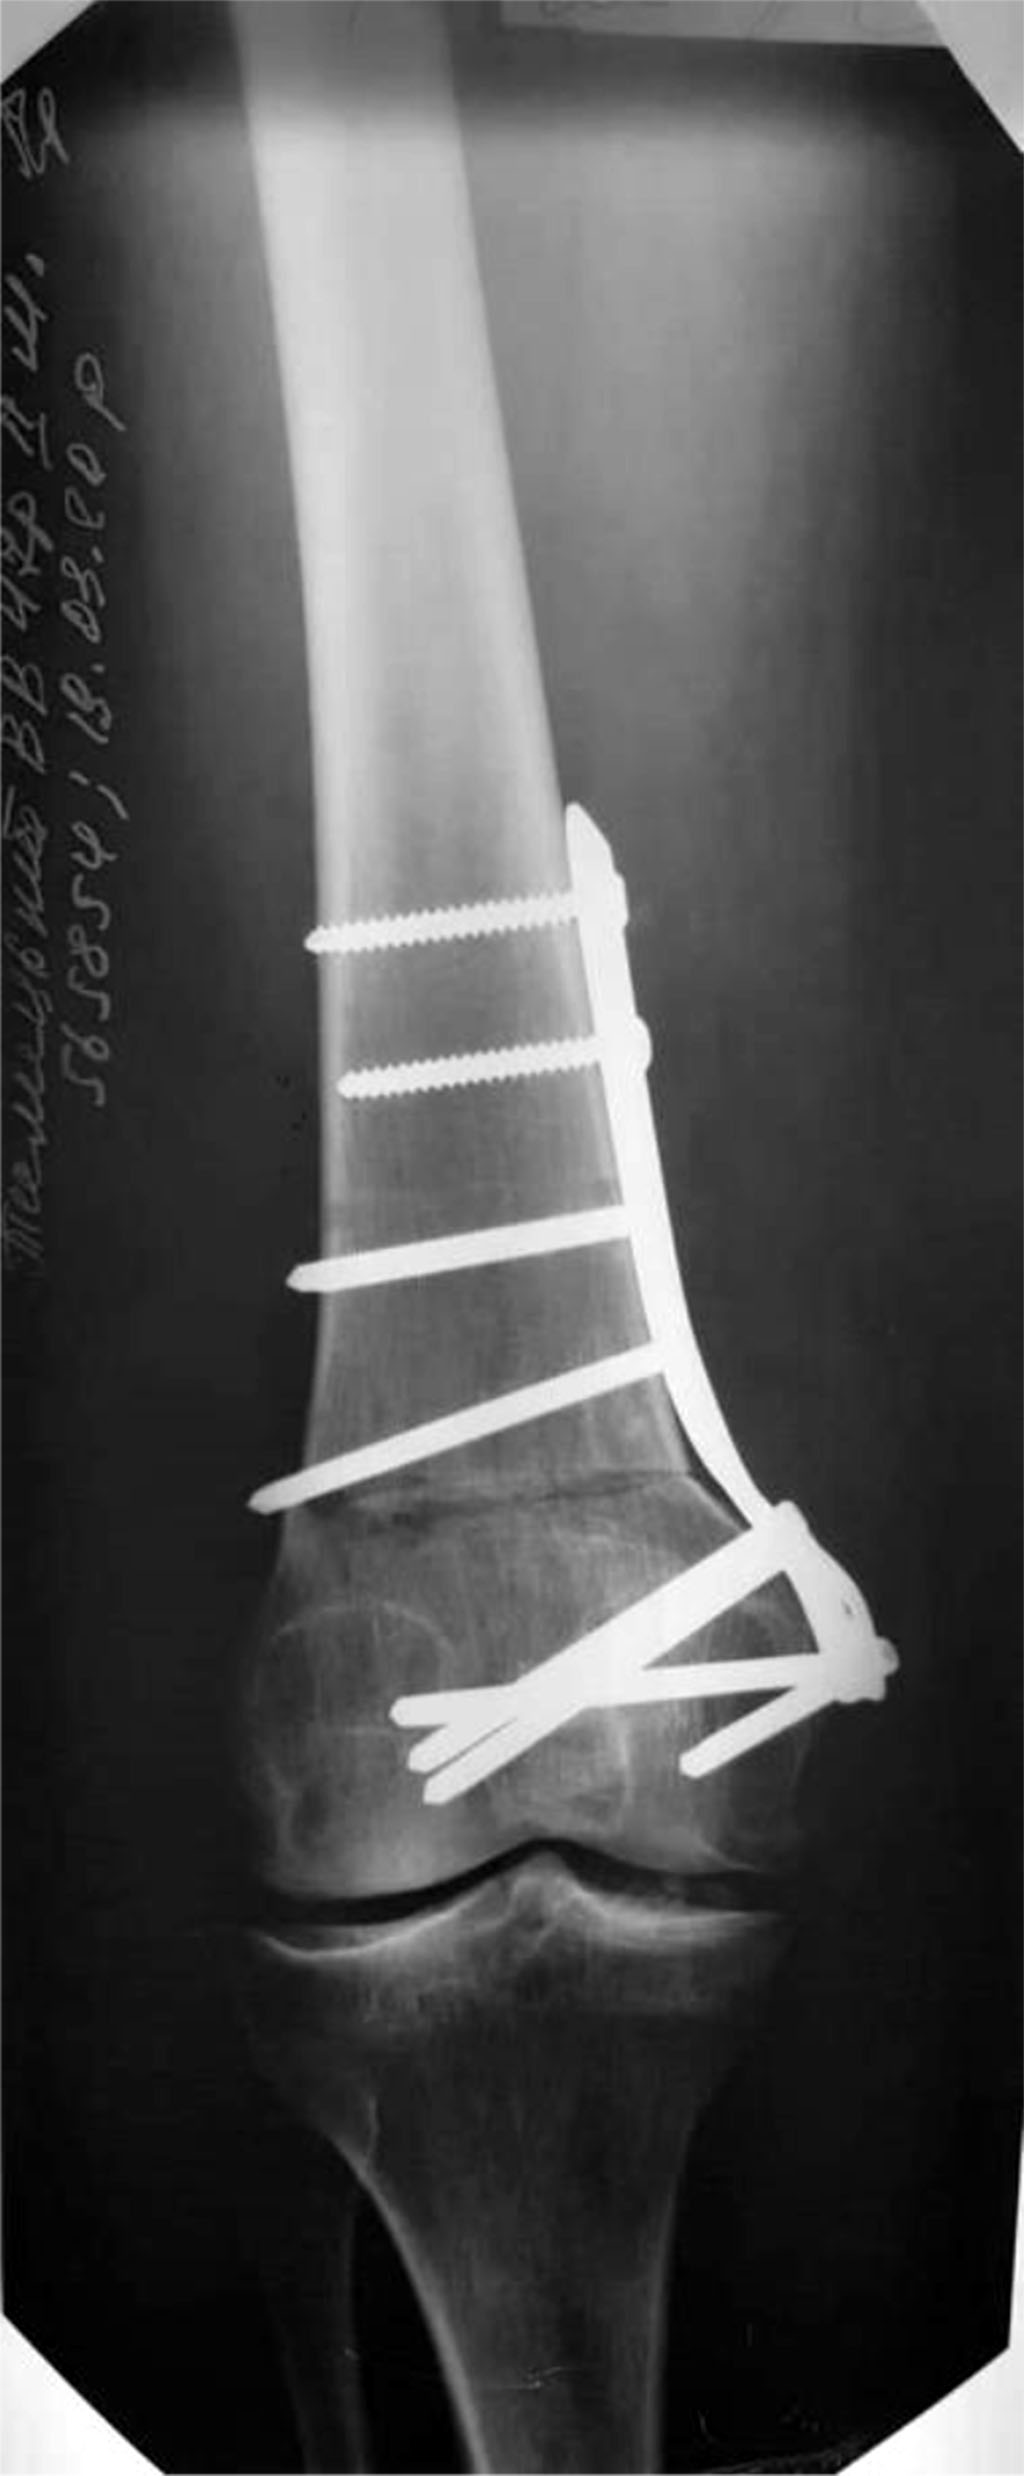

The patient underwent supracondylar resection varus osteotomy of the right femur (Fig. 6).

Figure 6. X-ray of the knee joint after carrying out supracondylar resection varus osteotomy of the right femur. With MOC LCR - plate.